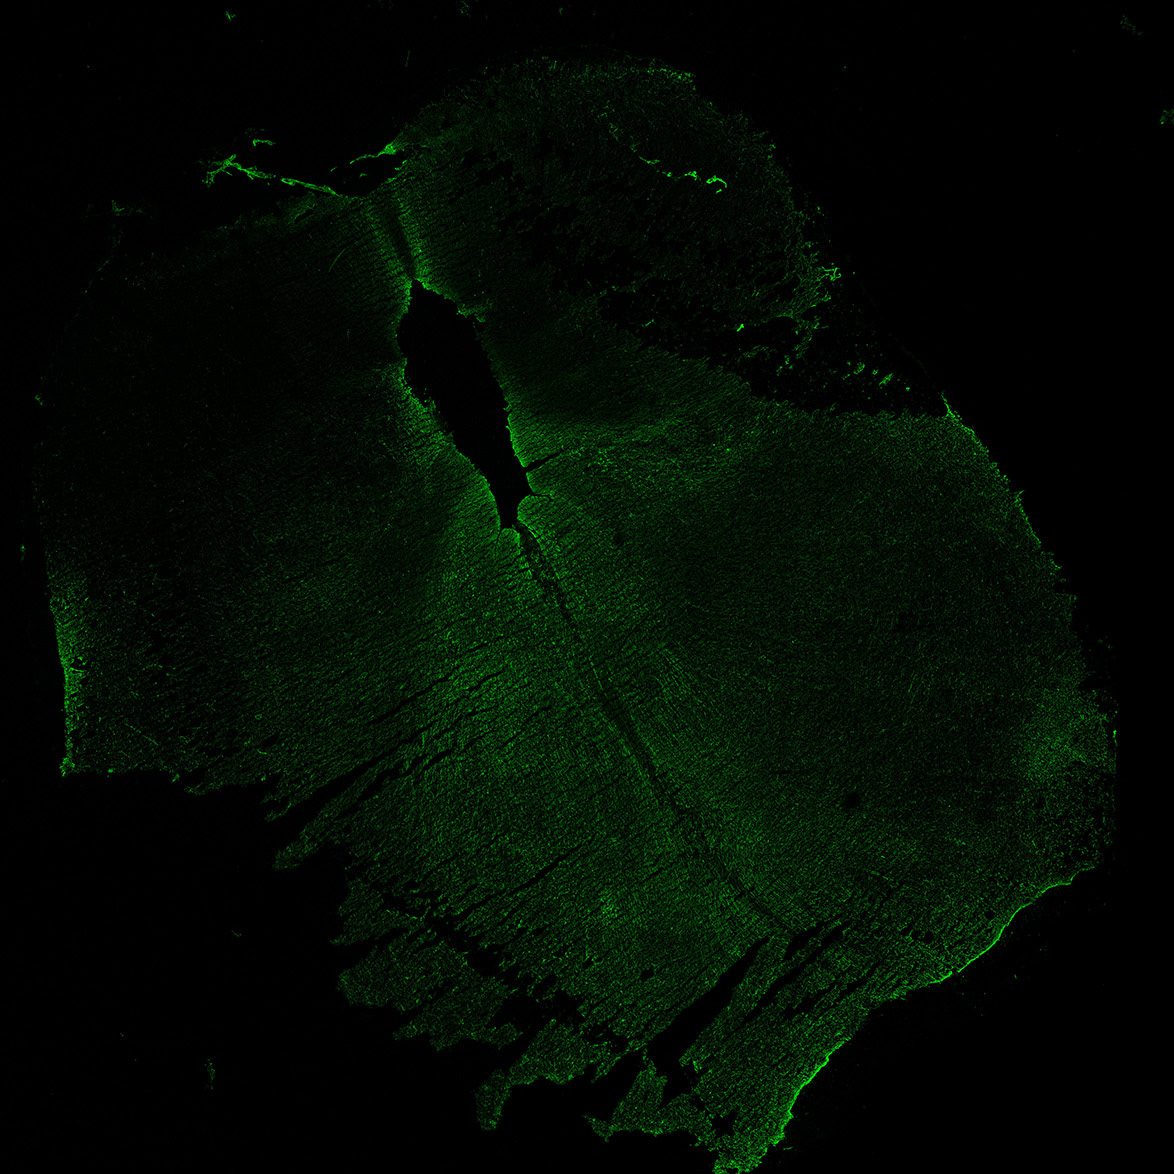

MAP2

6PCW human midbrain